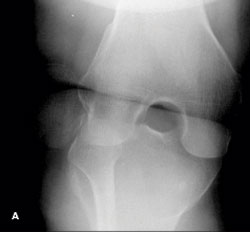

Outcome of this case. The patient’s dislocation was reduced externally. A frontal radiograph of the knee obtained after the reduction shows normal alignment of the patella and the distal femur (D). This is confirmed by a post-reduction lateral view (E). At 3 months, the patient has not had a recurrence.